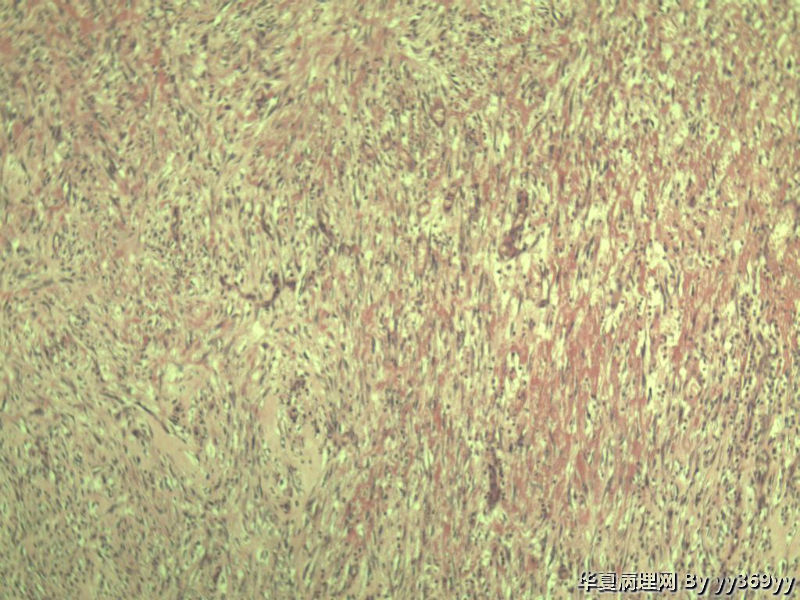

恶性的血管瘤??

男 30岁 小肠一段,肠管严重粘连可见一体积为 2.5 × 2 × 1.5 cm3的肿块,切面灰白,实性,质中

恶性的血管瘤??图2

肿块确切位置?图片颜色不正,需要考虑的有:脂肪坏死/腹腔纤维瘤病/炎性肌纤维母细胞瘤等。

纤维瘤病?

还有GIST需要鉴别